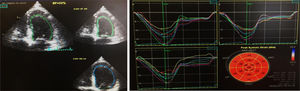

Durante o internamento na Enfermaria de Cardiologia, um cateterismo cardíaco diagnóstico foi realizado, com coronárias sem lesões (Figura 2). Não havia história familiar de IC, miocardiopatia ou morte súbita. O doente negava história recente de infeção viral ou bacteriana e nunca havia viajado para fora do país. O estudo laboratorial foi negativo, nomeadamente para vírus da imunodeficiência humana e hepatotrópicos. A função tiroideia não demonstrava alterações (avaliações prévias ao longo do seguimento na consulta de diabetes também normais), não tendo sido avaliados anticorpos antitiroideus neste contexto. Ressalvam‐se ainda outros parâmetros laboratoriais ao longo do internamento: hemoglobina (Hb) à admissão de 15g/dl, com nadir de 13g/dl, sem perdas hemáticas objetivadas; sem ferropénia funcional ou absoluta (Ferritina 326ng/mL) e sem défice de ácido fólico ou vitamina B12 (5,9ng/mL e 590pg/mL, respetivamente); vitamina B1 avaliada por protocolo nos doentes com IC / disfunção ventricular esquerda de 28ng/mL (N 16‐48). Sete dias após admissão hospitalar, um novo ETT foi realizado: ventrículo esquerdo não dilatado, com compromisso ligeiro da função sistólica (FEj estimada em 46%), com strain global longitudinal ligeiramente reduzido (‐16%) (Figura 3). Foi proposta a realização de ressonância magnética cardíaca, que o doente recusou. À data de alta hospitalar, o doente encontrava‐se em NYHA I, com proBNP de 448pg/ml, e medicado com Ramipril 2,5mg/dia e Bisoprolol 5mg/dia, além de insulina lenta para administração bidiária, tendo sido proposto seguimento em consulta de cardiologia e consulta hospitalar de diabetes.